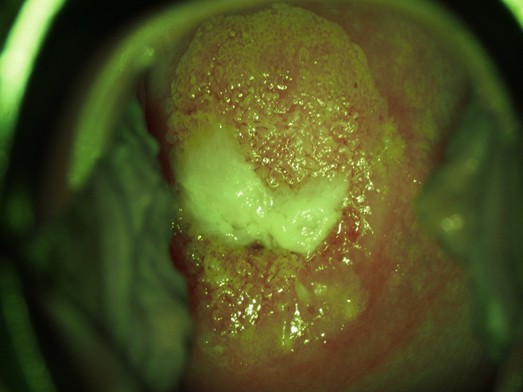

その後、子宮頸部に3%酢酸溶液を塗ります。特に痛みはありませんが、お酢のような臭いを感じるかと思います。1分間後、子宮頸部の異常部分が白くなり、細胞がどのような状態なのか詳しく知ることができ、観察しやすくなります。また、癌ができやすい部分、細胞がおかしな部分(移行帯)を知ることができます。

酢酸で白く染まった部分(組織)は、まだ癌なのかどうかはっきりはわかりません。でも、このちょっとしたおかしな部分をパンチという器具を使って掴み取ります。人によってはこの時痛みが生じます。大体は1ヶ所だけではなく、数ヶ所つかむため、痛みと出血があることが大半です。